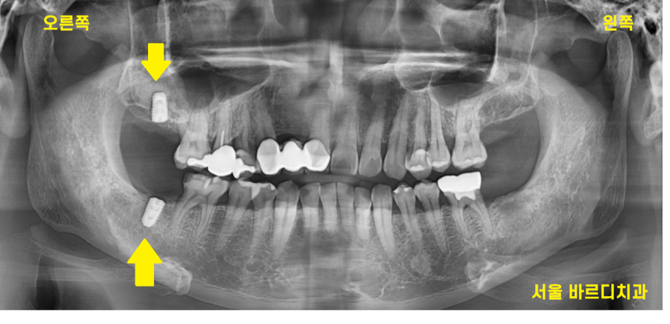

230711

오늘 환자분은 뼈가 없어서 씹는 힘이 다르게 느껴지셨기에

뼈 이식을 동반하여 수술을 진행하였습니다.